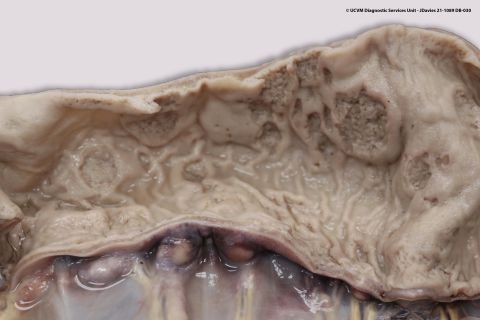

Specimen: Lymph node

Shown: Pyogranulomatous lymphadenitis Rhodococcus Equi.